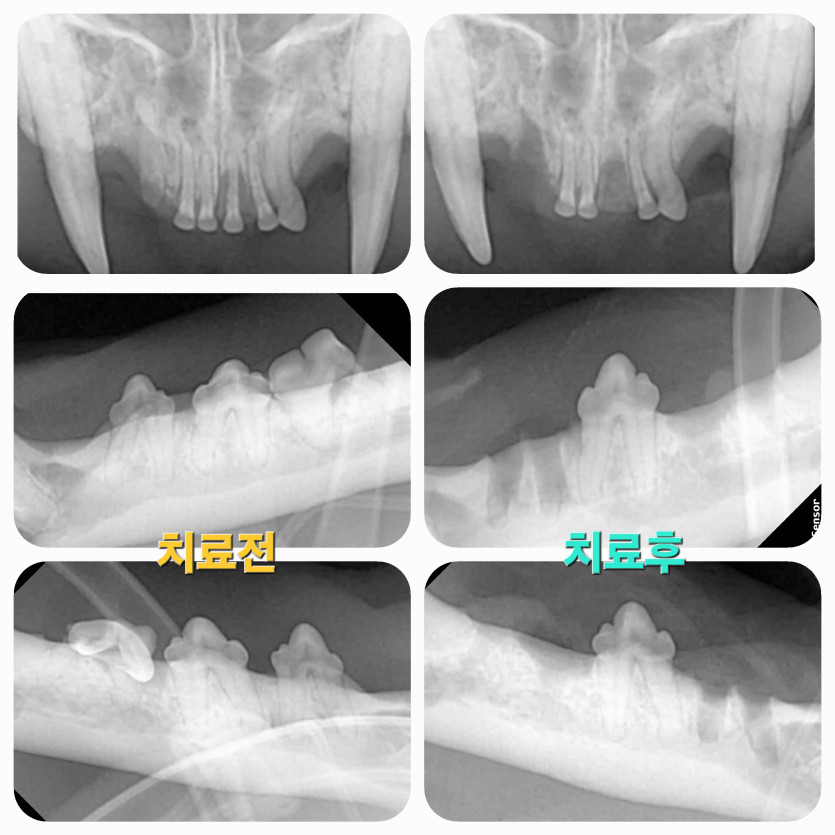

율이의 고양이 치아흡수 치료후기

원장님이랑 간호사 선생님들 너무 친절하고

여기 안 왔으면 애기 이빨 안 좋았던 것도 그냥 넘어 갔을 텐데

진료 꼼꼼히 잘 봐주셔서 감사합니다.